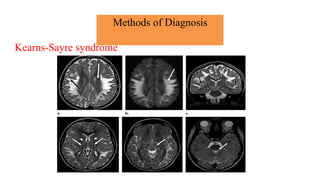

Brain magnetic resonance imaging

• Magnetic resonance imaging and spectroscopy are important tools in the diagnosis of

mitochondrial disorder.

• Brain atrophy is common in children with mitochondrial disease.

• Basal ganglia calcification are common in KSS and MELAS.

• Diffuse signal abnormalities of the white matter are characteristic of

KSS and myoneurogastrointestinal encephalopathy (MNGIE).

Methods of Diagnosis

Brain magnetic resonance imaging and spectroscopy

• The diagnosis of MELAS can be aided by the clinical association of stroke-like episodes with

radiological lesions that do not conform to the anatomical territories of blood vessels and

predominantly involve cortical gray matter.

• The initial or predominant lesions in MELAS are characteristically in the parietal- occipital

region.

• Leigh syndrome characteristically shows bilateral hyperintense signals on T2- weighted and

fluid-attenuated inversion recovery (FLAIR) MRIs in the putamen, globus pallidus and thalamus.

• MRS often detects lactate accumulation in the CSF and in specific areas of the

brain.

Kearns-Sayre syndrome